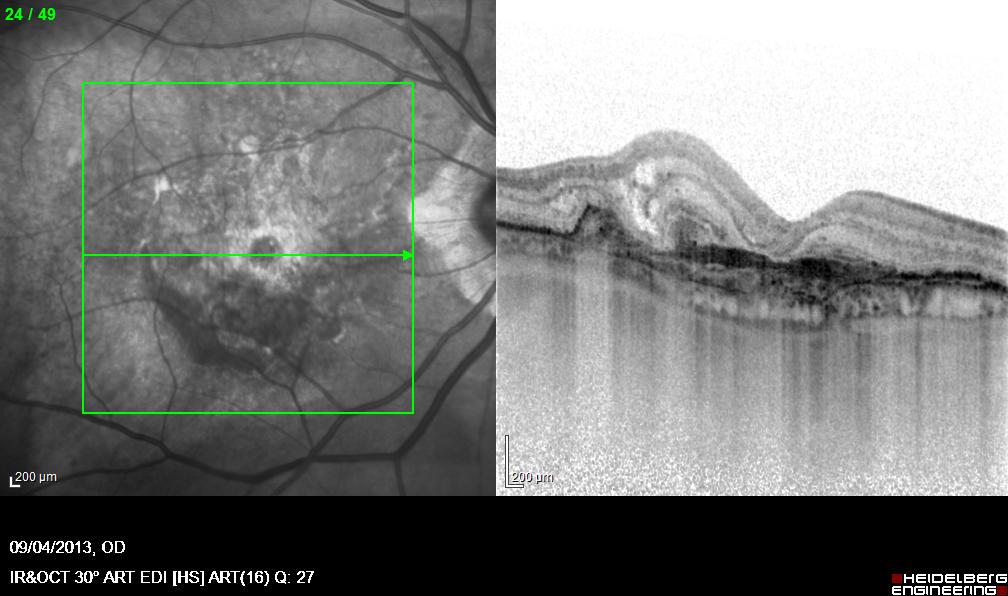

Oltre alle attività chirurgiche, il Dott. Acquaviva si avvale di tecnologie diagnostiche moderne per valutare in modo accurato lo stato di salute degli occhi. Esami come la tomografia a coerenza ottica (OCT), la pachimetria corneale e la misurazione del campo visivo sono strumenti fondamentali per un inquadramento completo e per la definizione del percorso terapeutico più efficace.